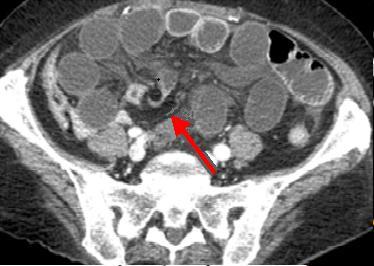

| Hernie inguinale etrangle : Image

d'engage du grele dans fossette inguinale

moyenne + image de distension de l'intestin au

dessus de l'obstacle ( fleche rouge ) . |

La TDM est tres

l'interet de presiser facilement le type de hernie :

hernie inguinale direct etrangle avec image de grele

en de dans des vaisseaux epigastriques .La TDM peut

differentiele avec les autres masses de la region

scrotale . |